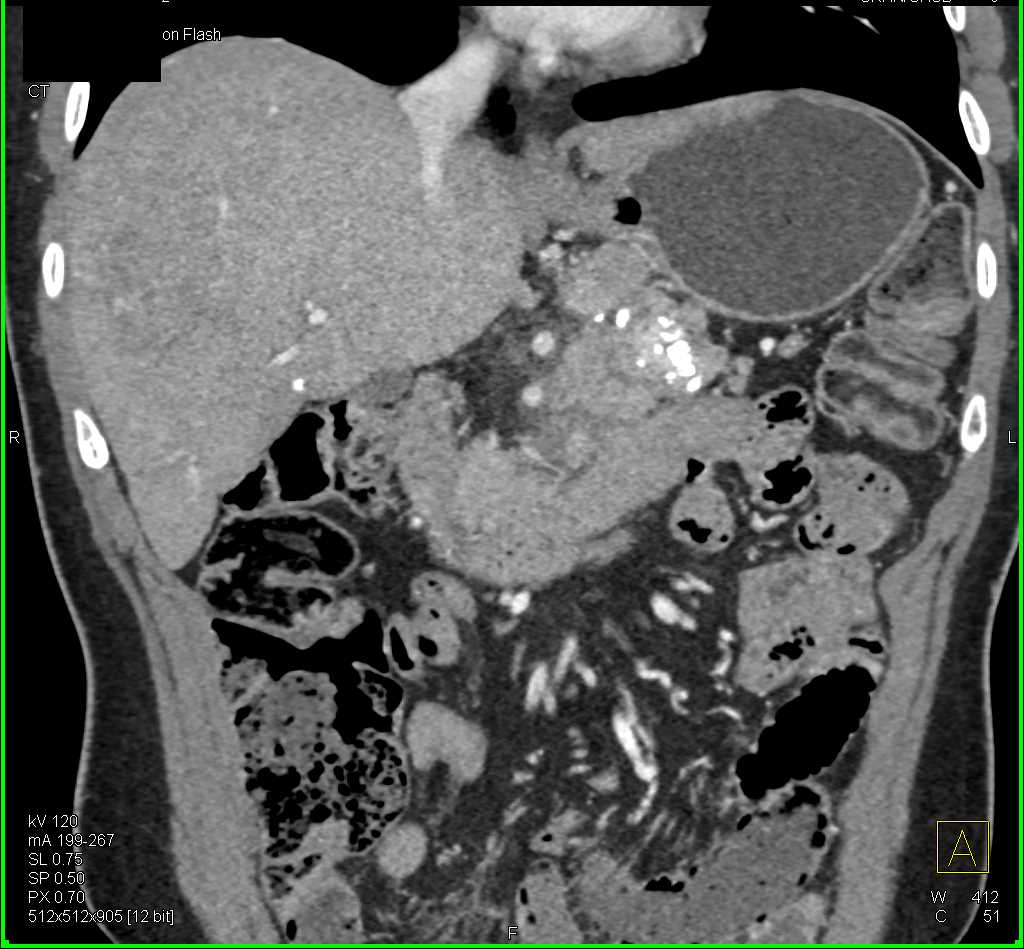

Neuroendocrine Tumor Pancreas